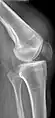

X-ray of a tear of the patellar tendon. On the left: The kneecap is pulled up. On the right: Significant dent in the soft tissue above the kneecap.